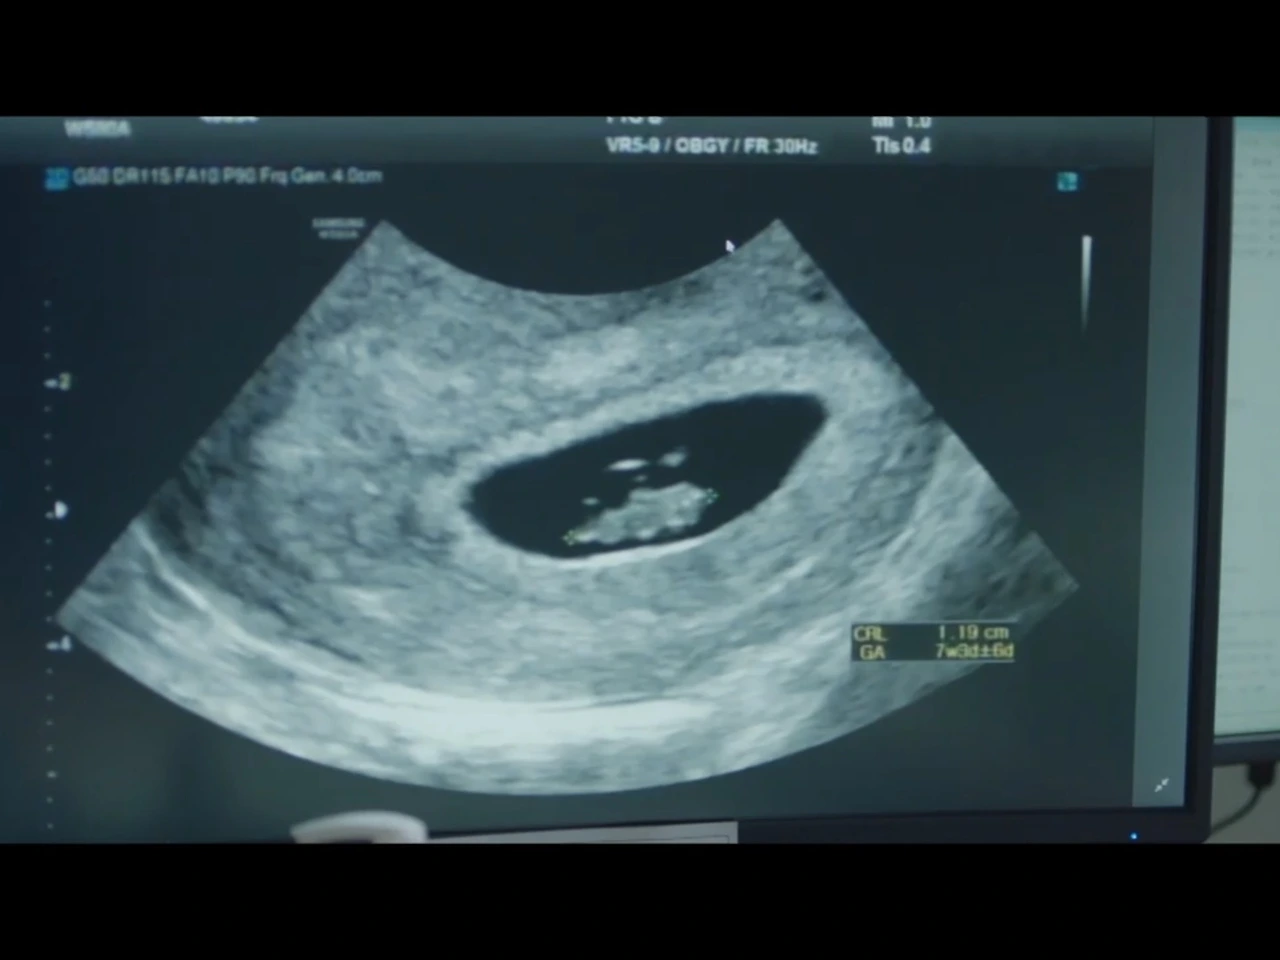

"이번이 세 번째 임신이시네요?

이전 두 번은 모두 유산하셨고.. 어, 임신 7주 차시네요."